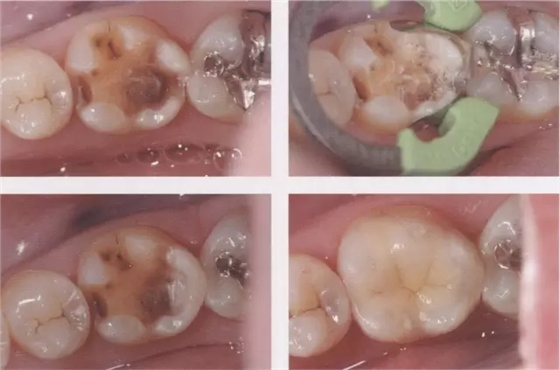

圖3鄰接面成形困難的病例。如圖所示右下7近中傾斜,窩洞成形的遠(yuǎn)中側(cè)有缺損(上左),所以遠(yuǎn)中部需要在齦下做很深的成形(上右),因而選擇在遠(yuǎn)中先進(jìn)行樹脂填充后(上右)。進(jìn)行MO窩洞修整后做全瓷嵌體試戴(下)。